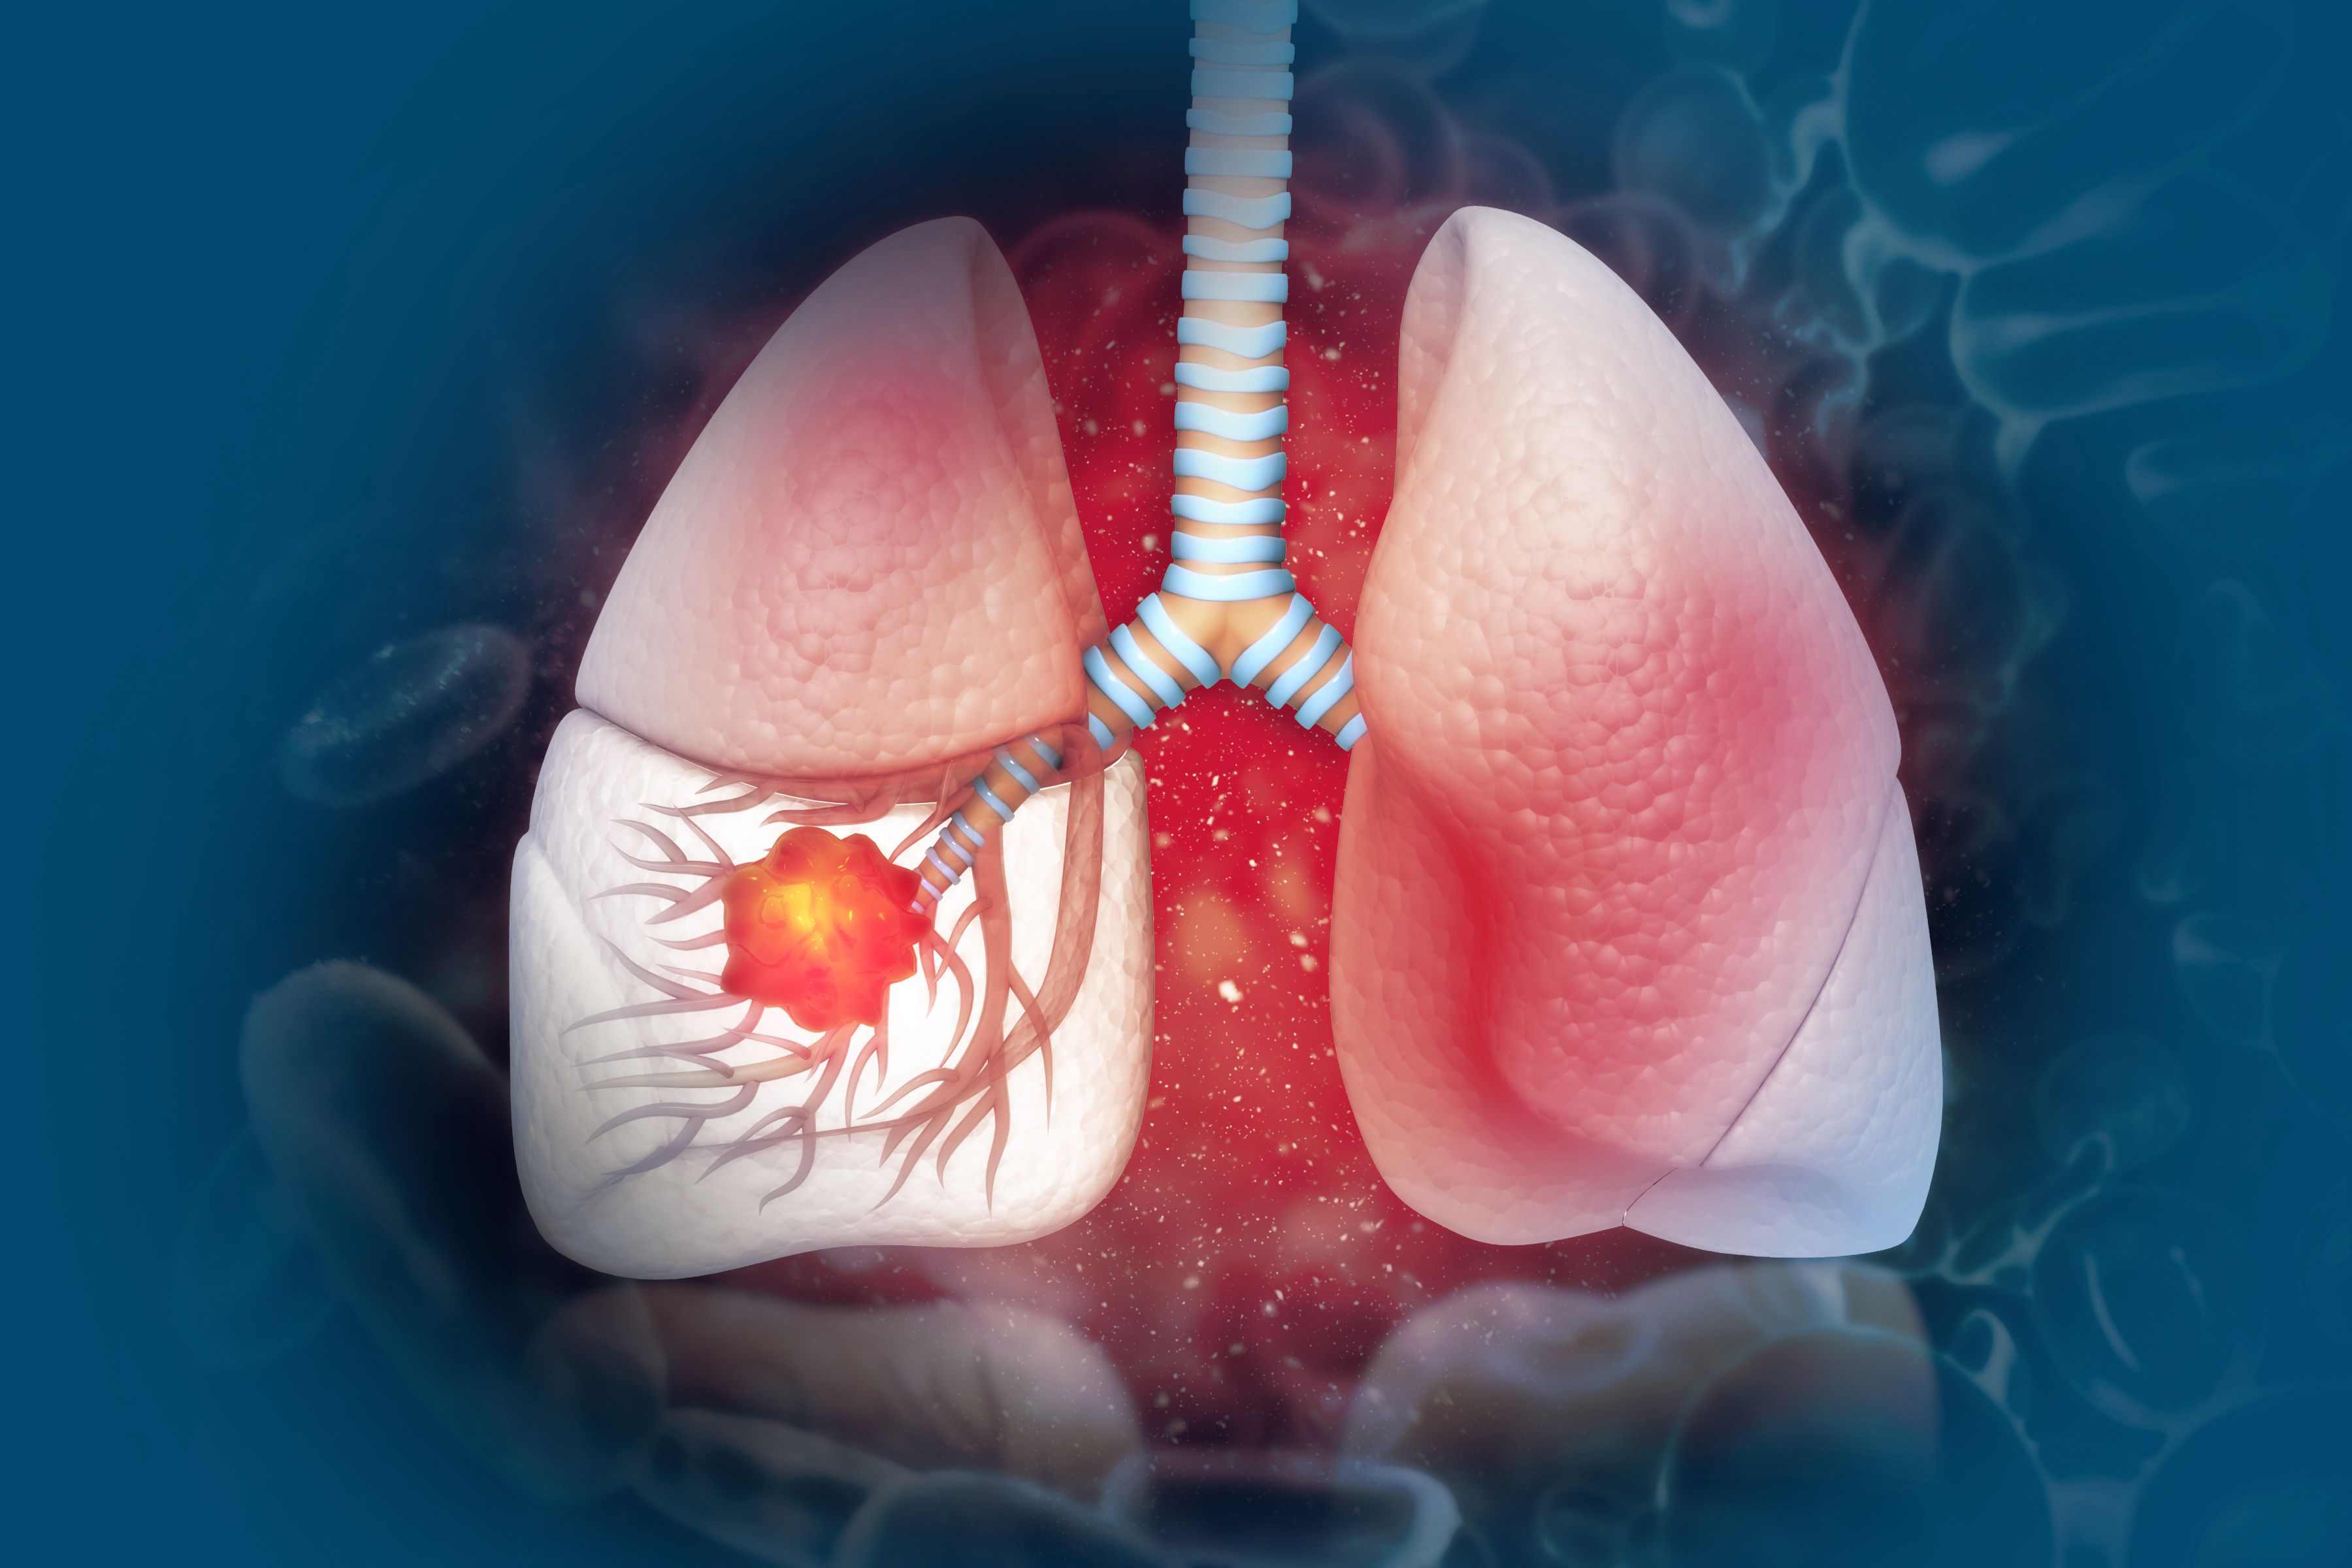

肺癌是我国发病率和死亡率最高的癌症之一,但许多人对它的认知仍存在误区,甚至因此延误了治疗或忽视预防。作为一名医生,我整理了临床中最常被问到的7大误区,并为大家揭开真相。

虽然吸烟是肺癌的首要危险因素(约85%的肺癌与吸烟相关),但不吸烟者也可能患肺癌。约15%-20%的肺癌患者从不吸烟,尤其是女性腺癌患者中比例更高。生活中如二手烟、厨房油烟、空气污染(如PM2.5)、氡气(家庭装修材料释放)等均可诱发肺癌。因此无论是否吸烟,都应远离油烟和雾霾,40岁以上人群建议定期做低剂量螺旋CT筛查。

近年来肺癌年轻化趋势明显,30-40岁患者并不罕见。年轻患者多与遗传基因突变(如ALK融合)、长期熬夜、压力大、免疫力下降相关。并且年轻人症状不典型,确诊时往往已到中晚期。因此,无论年龄,若有长期吸烟史、家族史或持续呼吸道症状,务必及时筛查。不要等到出现明显症状时,才追悔莫及。